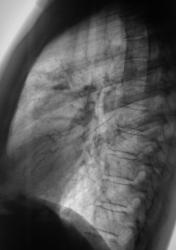

После расшифровке флюорограмм пациент "взят на контроль" - 1, 2.

Произведено стандартное дообследование пациента - рентгенография (3, 4, 5) и томография (6, 7, 8, 9, 10, 11). Была заподозрена онкология, однако изменения на томограмме - срез 7 см. (9, 10, 11), склонили нас в пользу изменений воспалительного генеза. Было решено провести адекватную противовоспалительную терапию. После проведения противовоспалительной терапии был произведен рентген-контроль ( 12, 13, 14, 15).